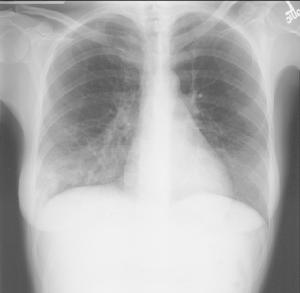

肺部常見的疾病有:氣胸、肺大泡、肺氣腫、肺部陰影(嚴格講不算單獨疾病,但臨床上常作為多種肺部占位病變的統稱)和肺癌,肺心病、呼吸衰竭、肺栓塞、肺膿腫、肺炎、新生兒肺炎、小兒肺炎、氣管炎、哮喘、肺結核、塵肺、間質性肺疾病、呼吸系統疾病等。

肺炎是肺實質和間質,由於多種病原體引起其他如放射、化學、免疫、過敏及藥物等因素亦能引起肺炎。肺膿腫